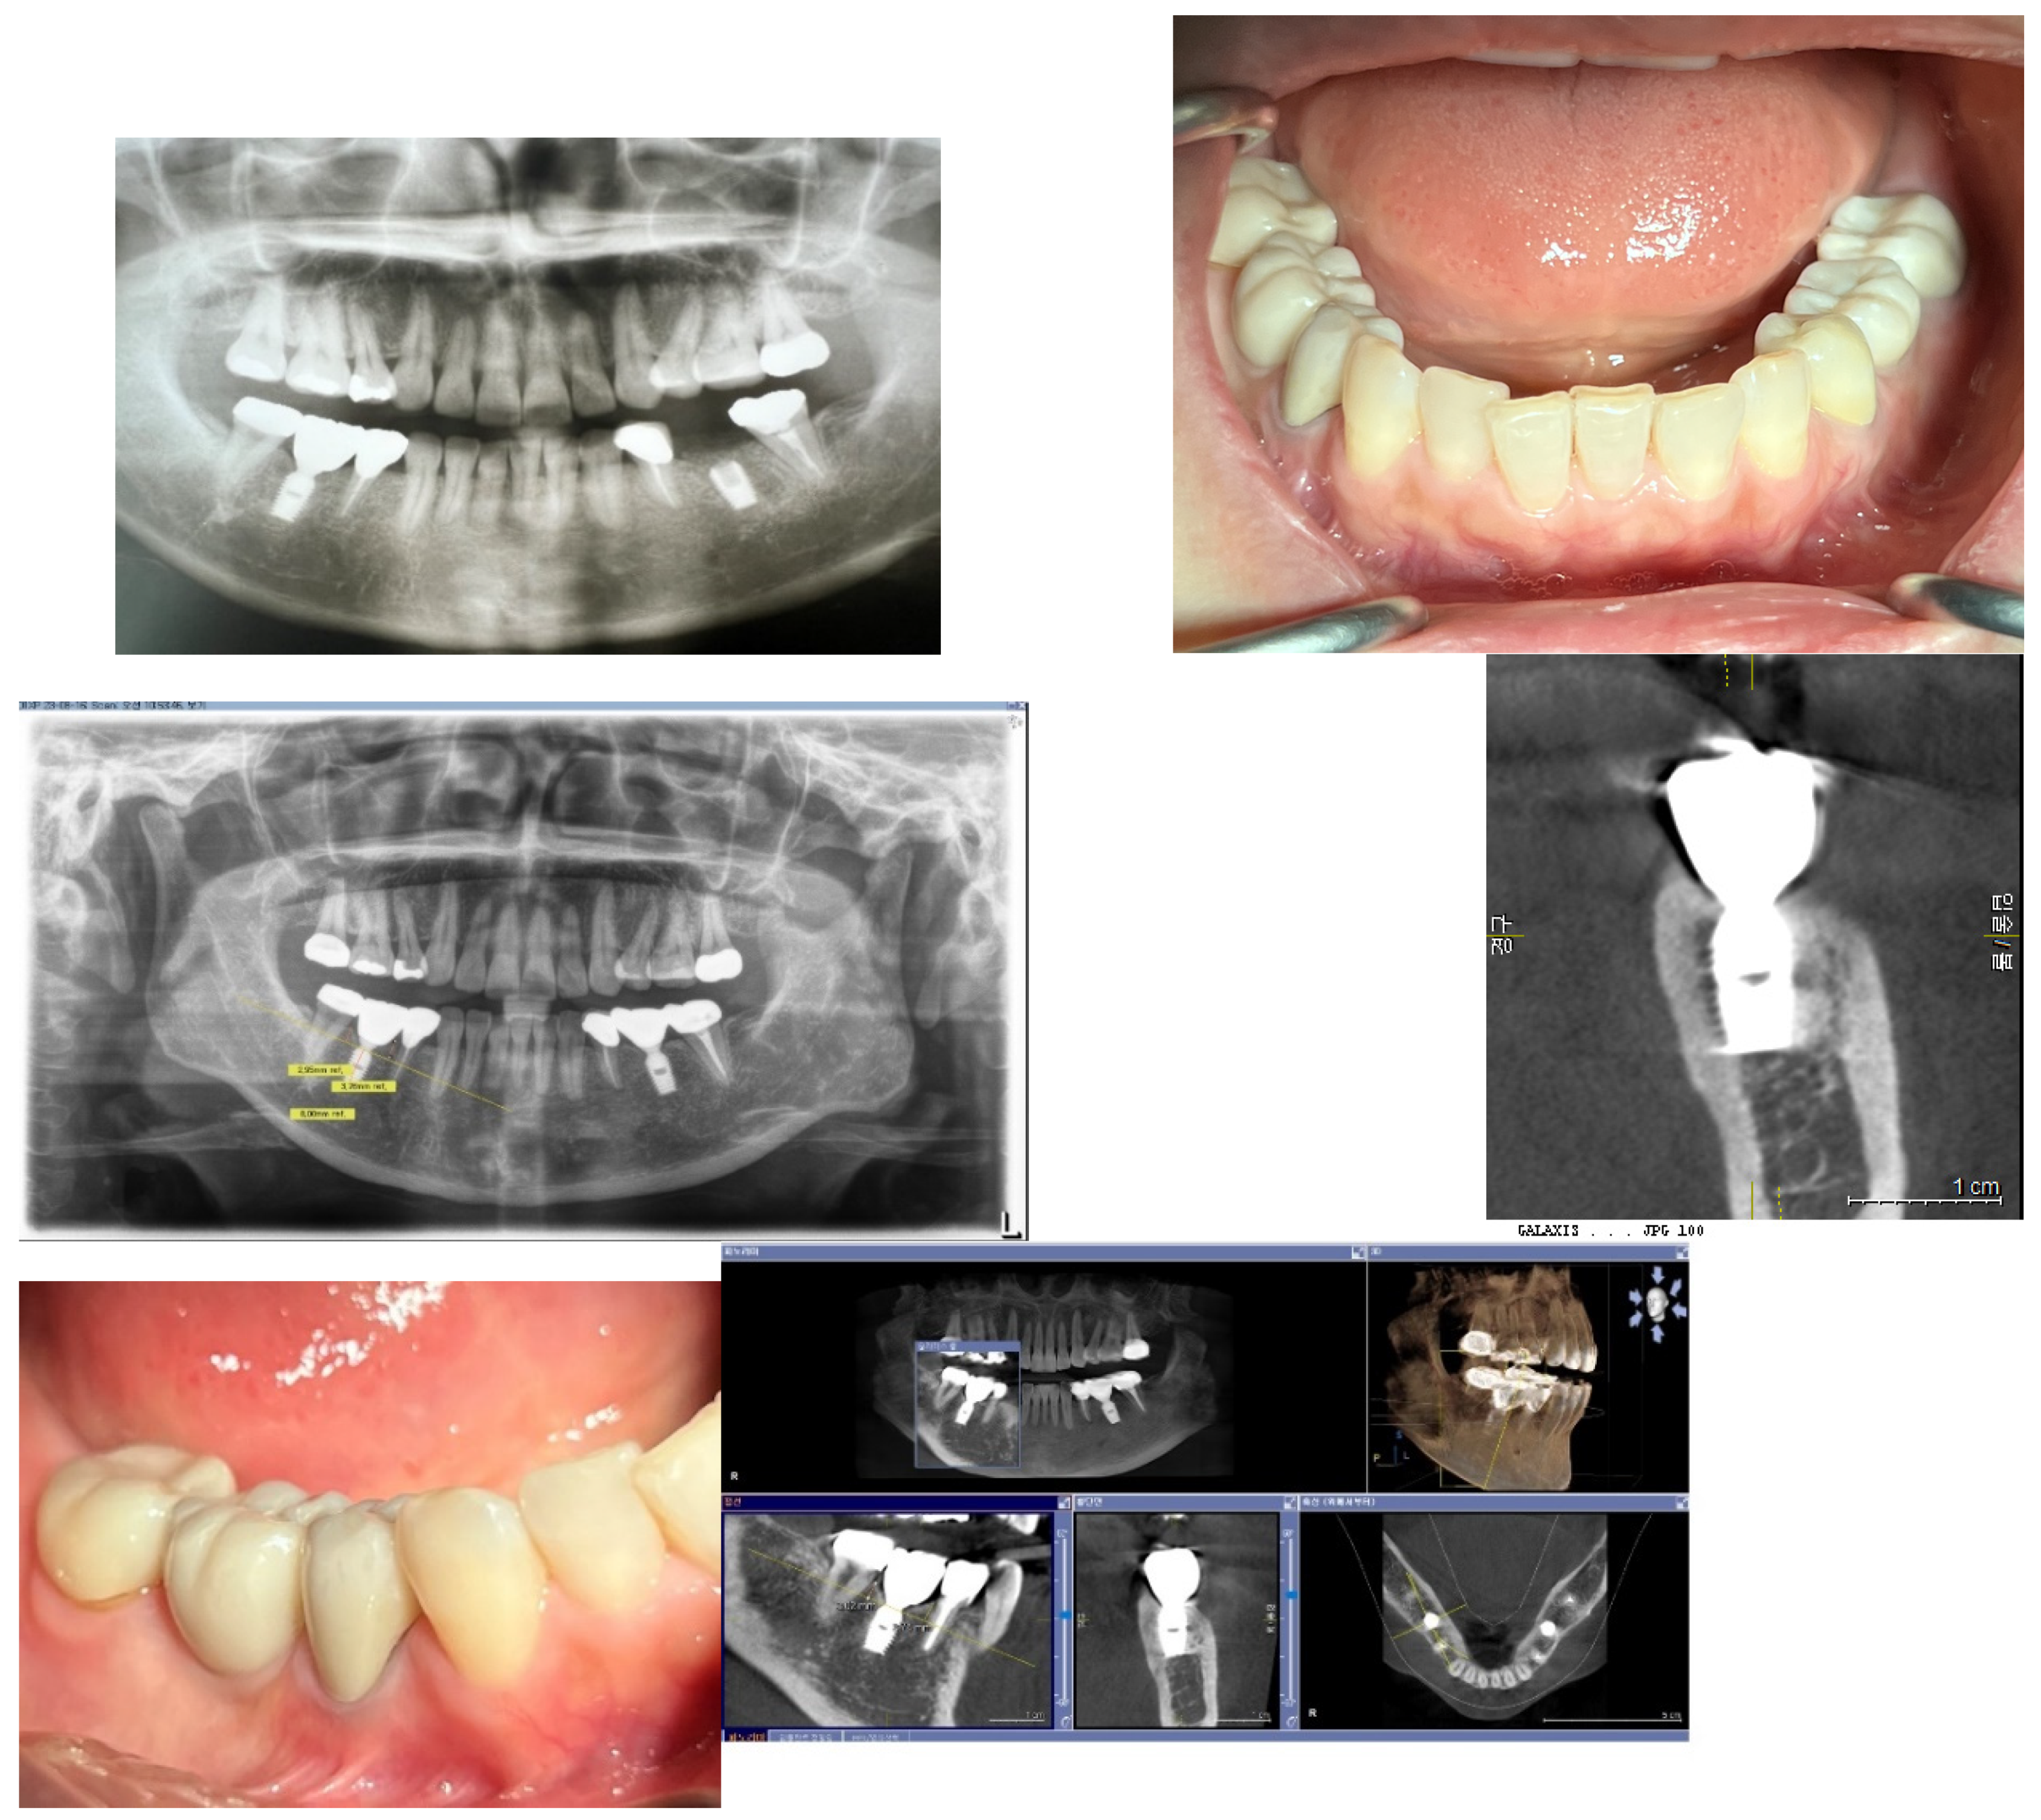

Calibration of CBCT: To ensure accuracy, the presentation plane of the CBCT was centered around the long axis of the fixture. This allowed for the confirmation of the fixture's size—both diameter and length—against its known original dimensions.

Figure 11. Calibration of CBCT Images. This figure demonstrates the calibration process where images are coordinated along the long axis of the fixtures. This alignment is crucial for accurate measurement and analysis, ensuring that the fixture dimensions are accurately reflected in the CBCT images.